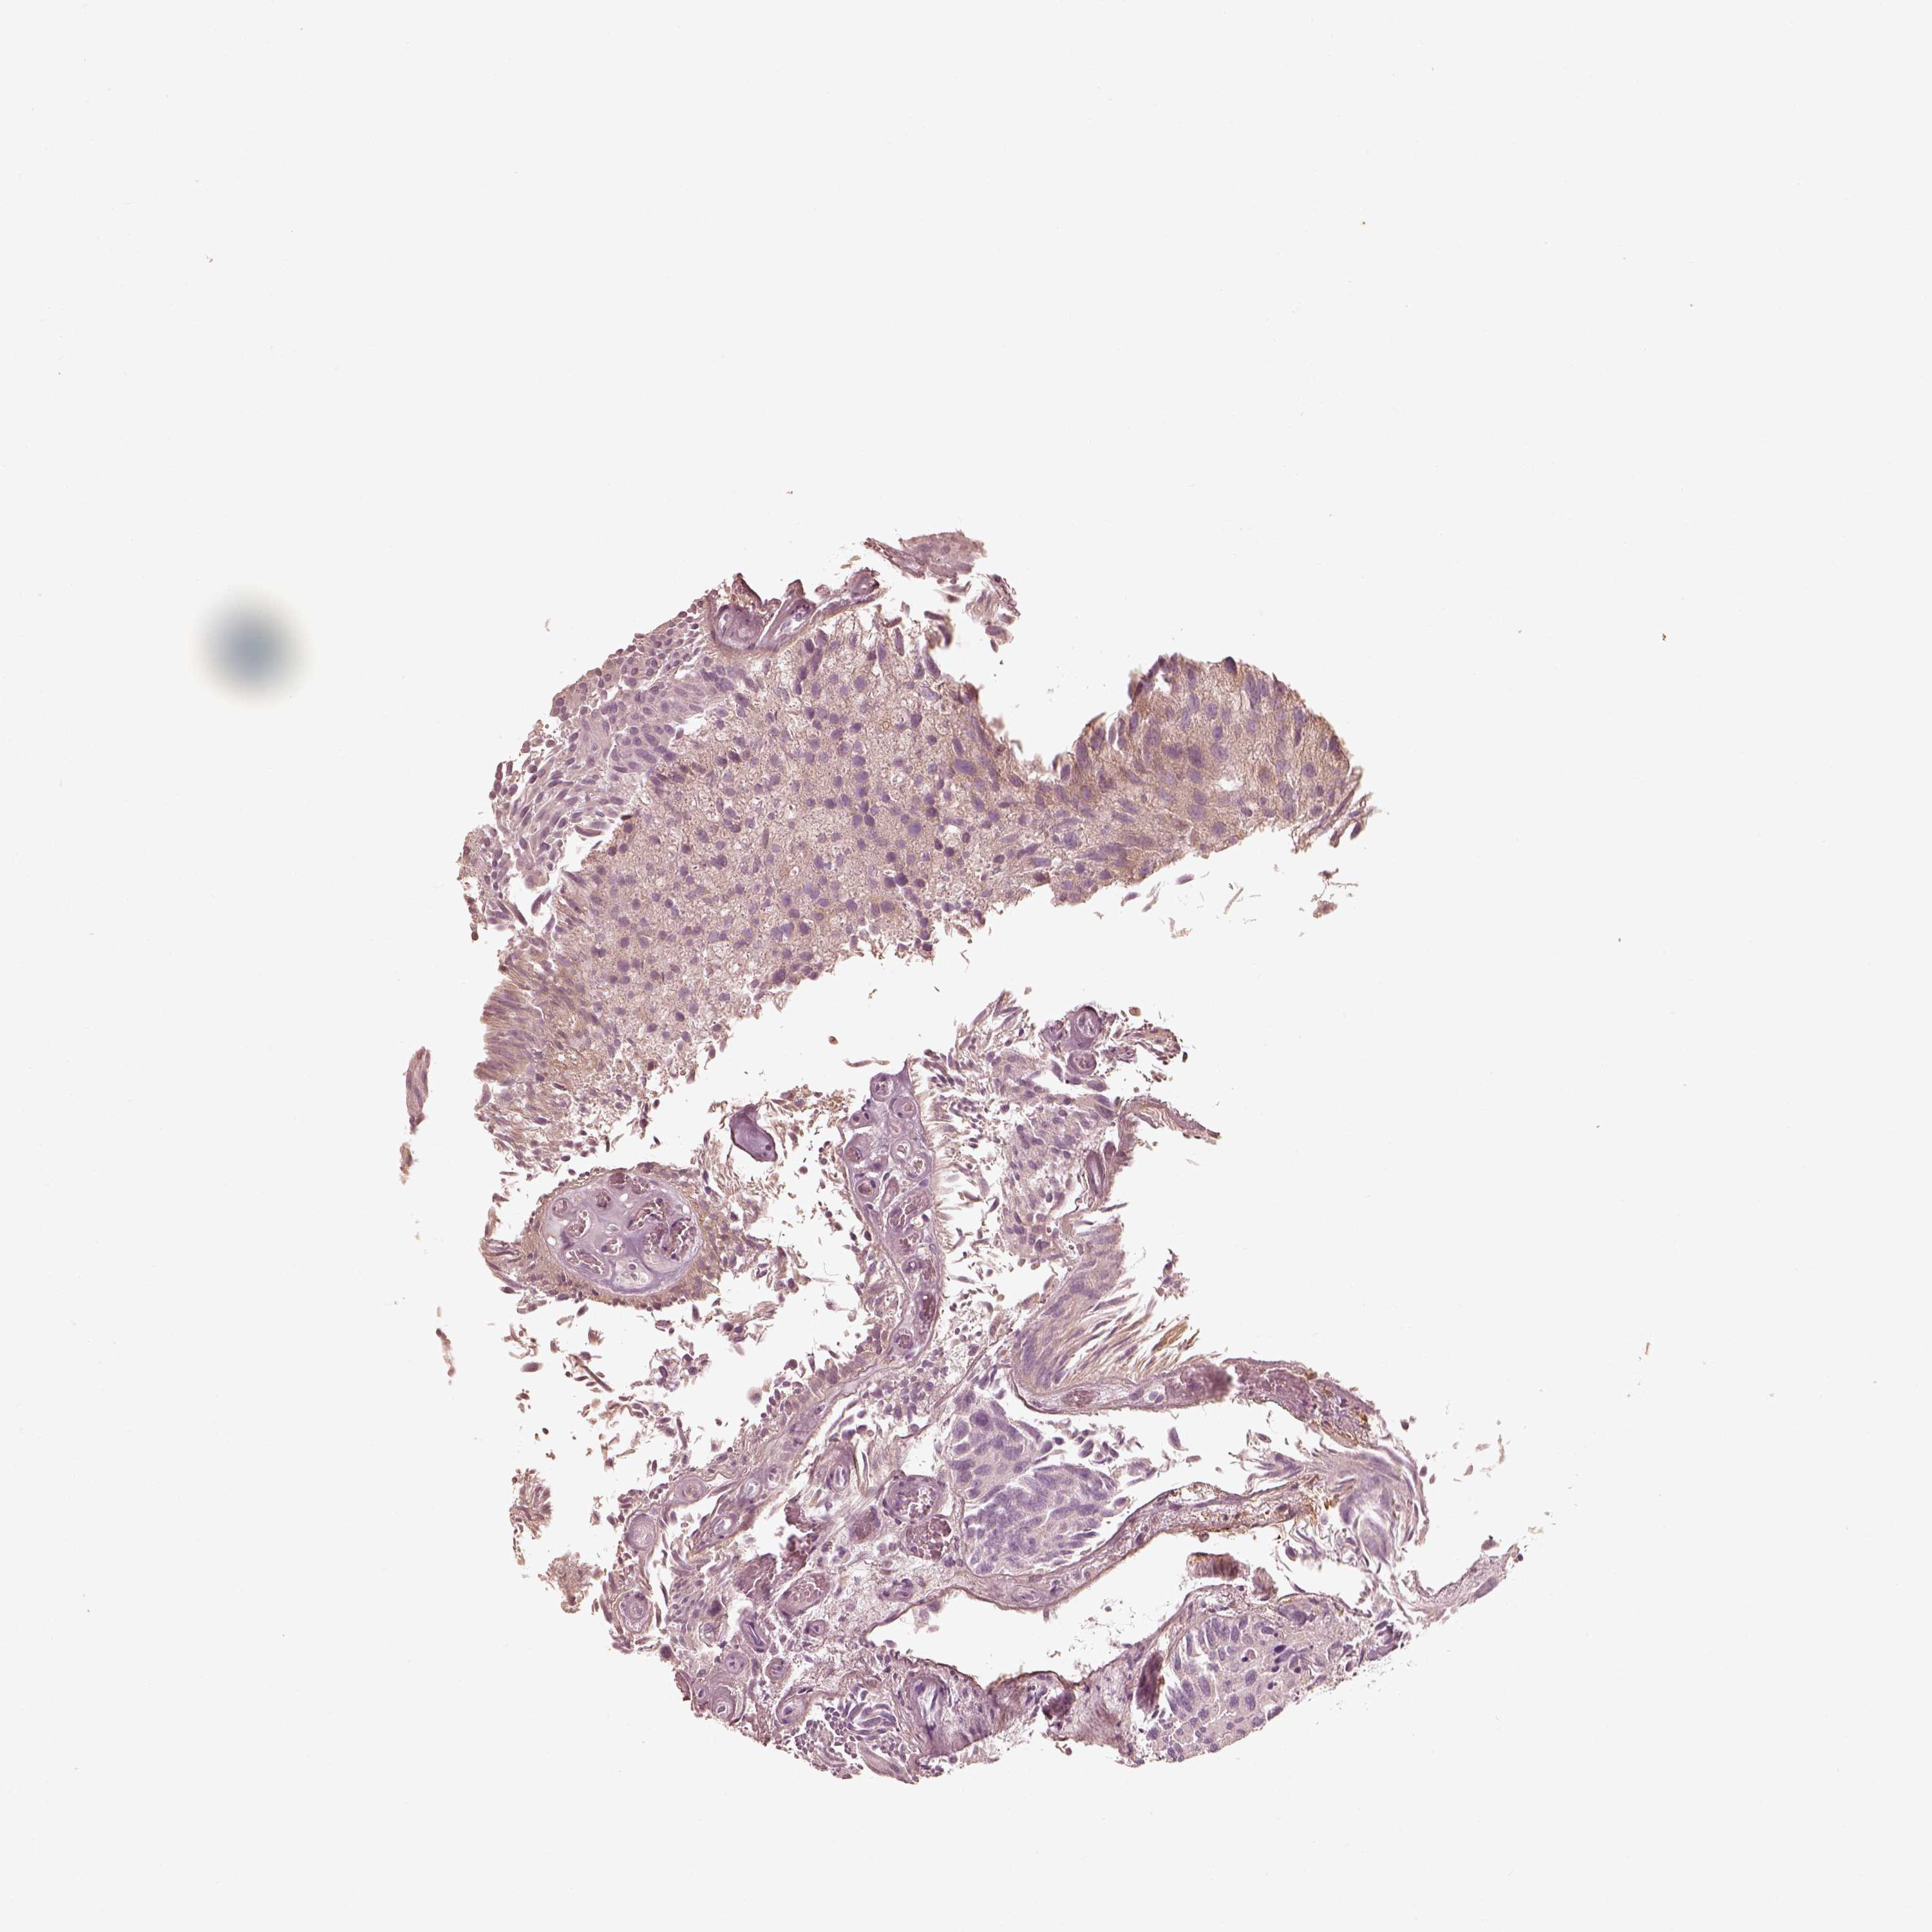

UROTHELIAL CANCER - Protein expressioni

A mouse-over function shows sample information and annotation data. Click on an image to view it in a full screen mode. Samples can be filtered based on level of antibody staining by selecting one or several of the following categories: high, medium, low and not detected. The assay and annotation is described here.

Antibody stainingi

Antibody staining in the annotated cell types in the current human tissue is reported as not detected, low, medium, or high, based on conventional immunohistochemistry profiling in selected tissues. This score is based on the combination of the staining intensity and fraction of stained cells.

Each image is clickable and will lead to virtual microscopy that enables deeper exploration of all samples and also displays staining intensity scores, fraction scores and subcellular localization as well as patient and tissue information for each sample.

Antibody HPA069520

Staining

High

Medium

Low

Not detected

Intensity

Strong

Moderate

Weak

Negative

Quantity

>75%

75%-25%

<25%

None

Location

Nuclear

Cytoplasmic/membranous

Cytoplasmic/membranous,nuclear

Urothelial carcinoma, High grade

Urothelial carcinoma, NOS

Urothelial carcinoma, Low grade